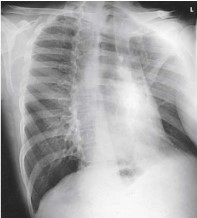

What projection, position, and anatomy is this?

Lateral decubitus for lungs, checking for fluid